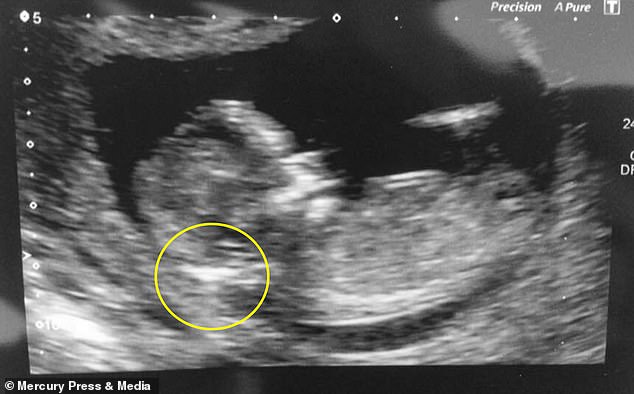

Η 22χρονη Jordan Squires από το Middlesborough, ισχυρίζεται ότι κατά την εξέταση των 12 εβδομάδων, ο γιατρός της της είπε ότι το μωρό που κουβαλούσε ήταν «πολύ πιθανό» να έχει σύνδρομο Down λόγω της μεγάλης ποσότητας υγρού στο πίσω μέρος του λαιμού του.

“Εκεί, ο γιατρός μας είπε το μωρό ήταν πολύ πιθανό να έχει σύνδρομο Downs λόγω της μεγάλης ποσότητας υγρού που υπήρχε στο πίσω μέρος του λαιμού του.”